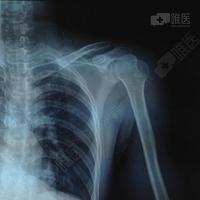

肩关节半脱位图片

肩关节脱位分型图片